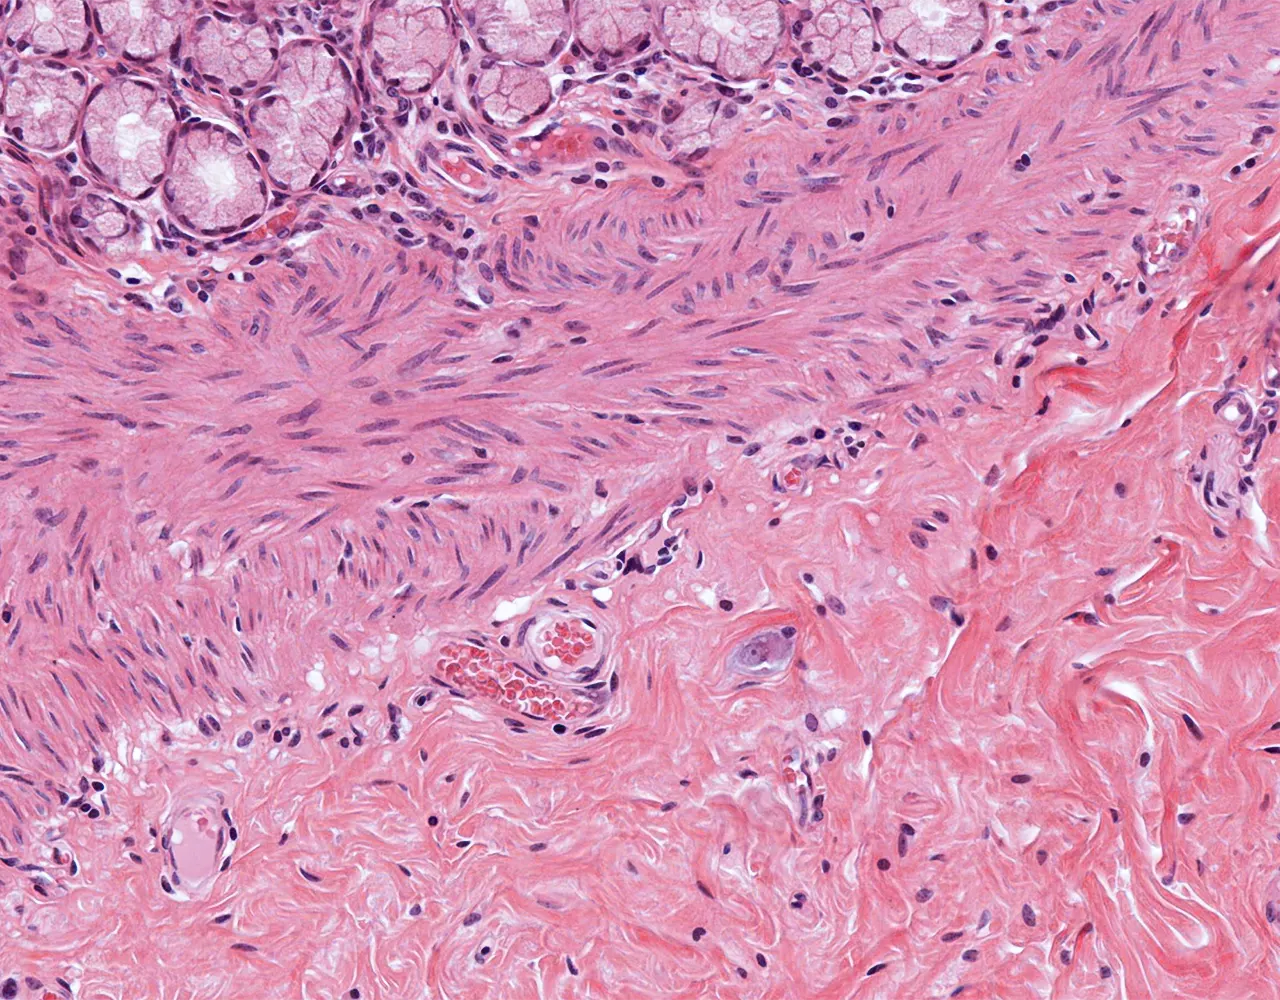

- The wall of the stomach is composed of four layers, from the innermost to the outermost: mucosa, submucosa, muscularis propria, and serosa.